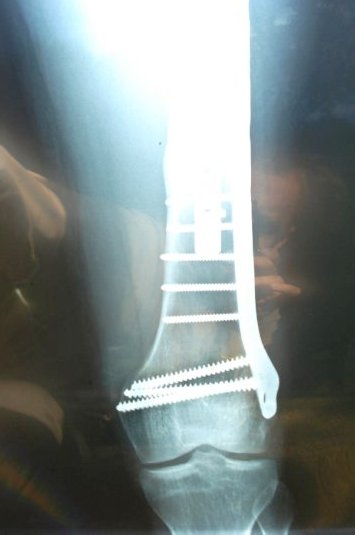

I was dragged for a bout 50 yards and my leg and hip were both crushed. Long story short – I have a small drawer of heavy-duty utensils bolted to my left femur. Unfortunately, I broke the first set and had to have the Super Duty set screwed in a year later.